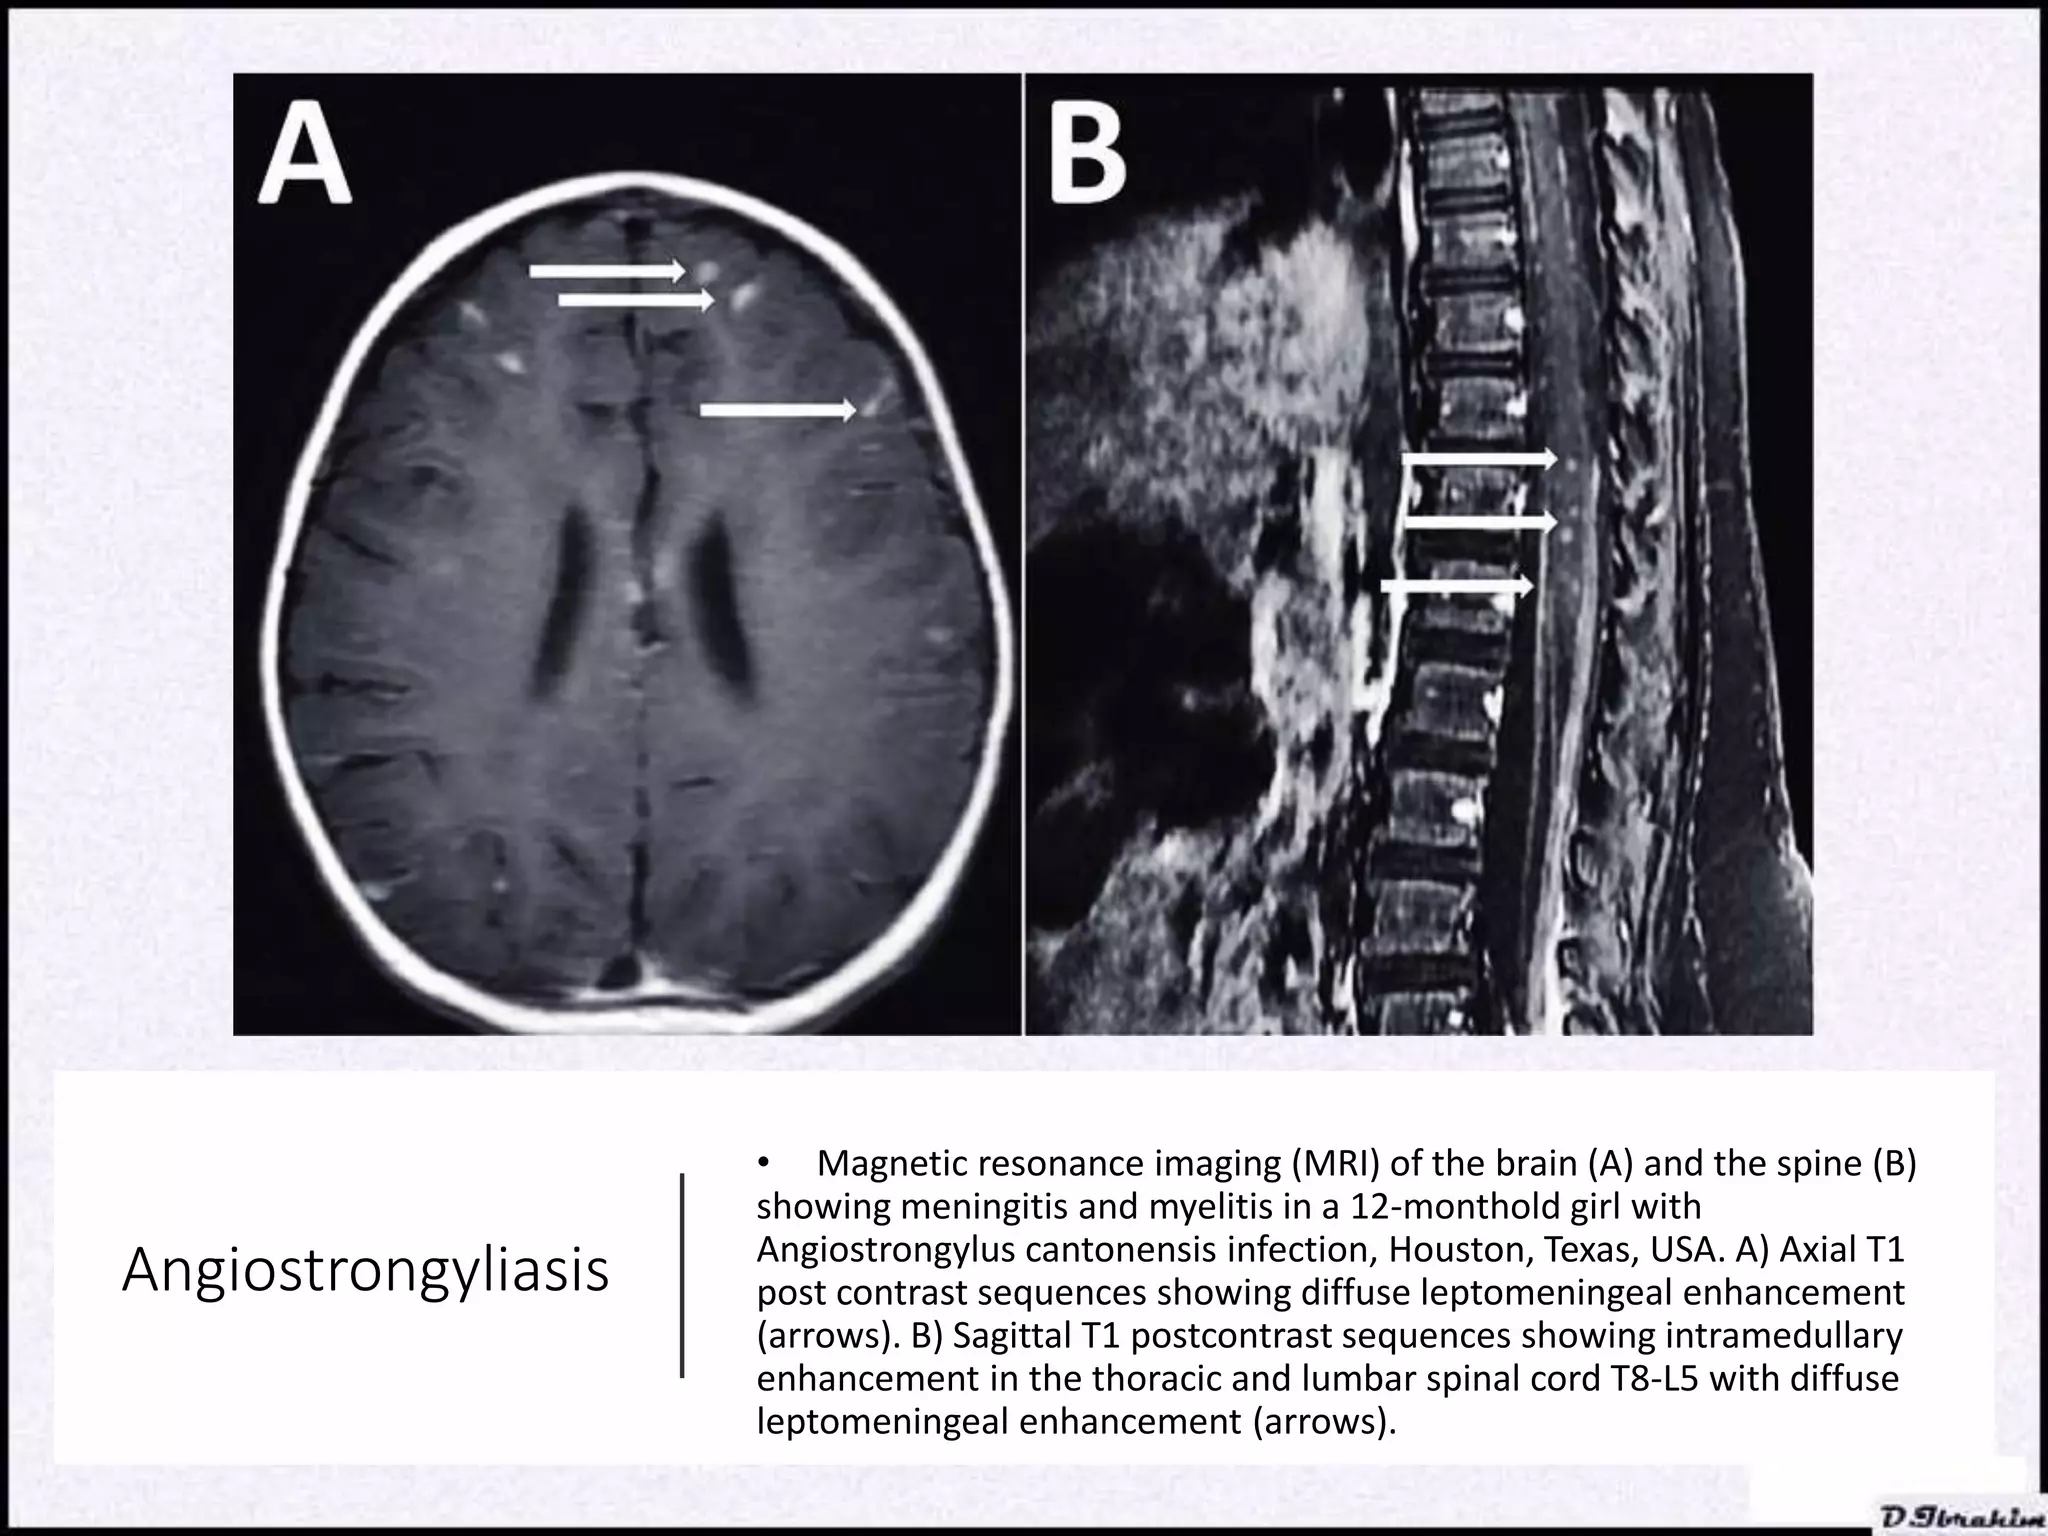

CNS Radiography for helminth infections.pptx